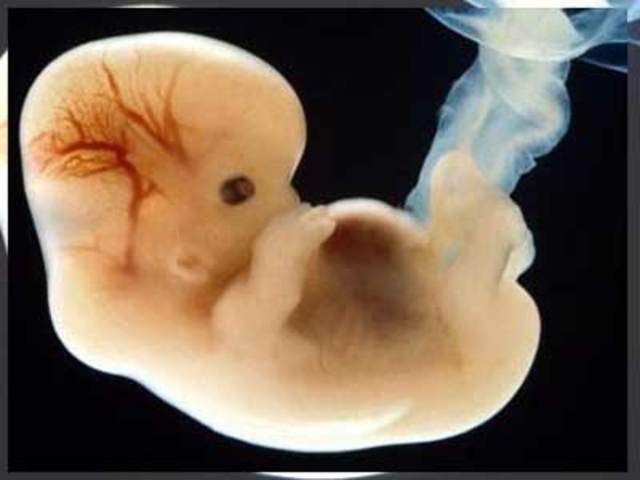

• Semana 8

Se termina el periodo embrionario y pasa a ser feto. Los dedos estan mejor definidos y la cabeza es mas grande que su cuerpo.